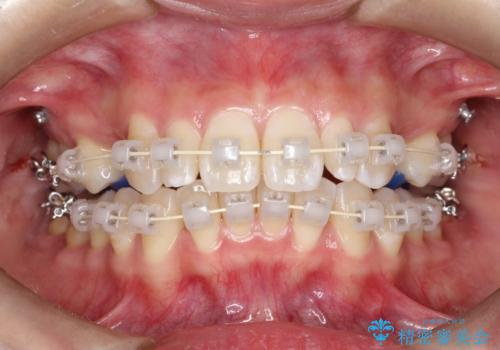

- 矯正装置

- 審美装置

上顎の歯が全体的に前方に位置しているのと、前から2番目の歯が通常よりも小さい矮小歯という状態でした。

出っ歯をなおすために上顎の前から4番目の歯を抜歯して、引っ込めるのと、前から2番目の歯に通常の大きさのオールセラミックを装着して整った歯並びにすることにしました。